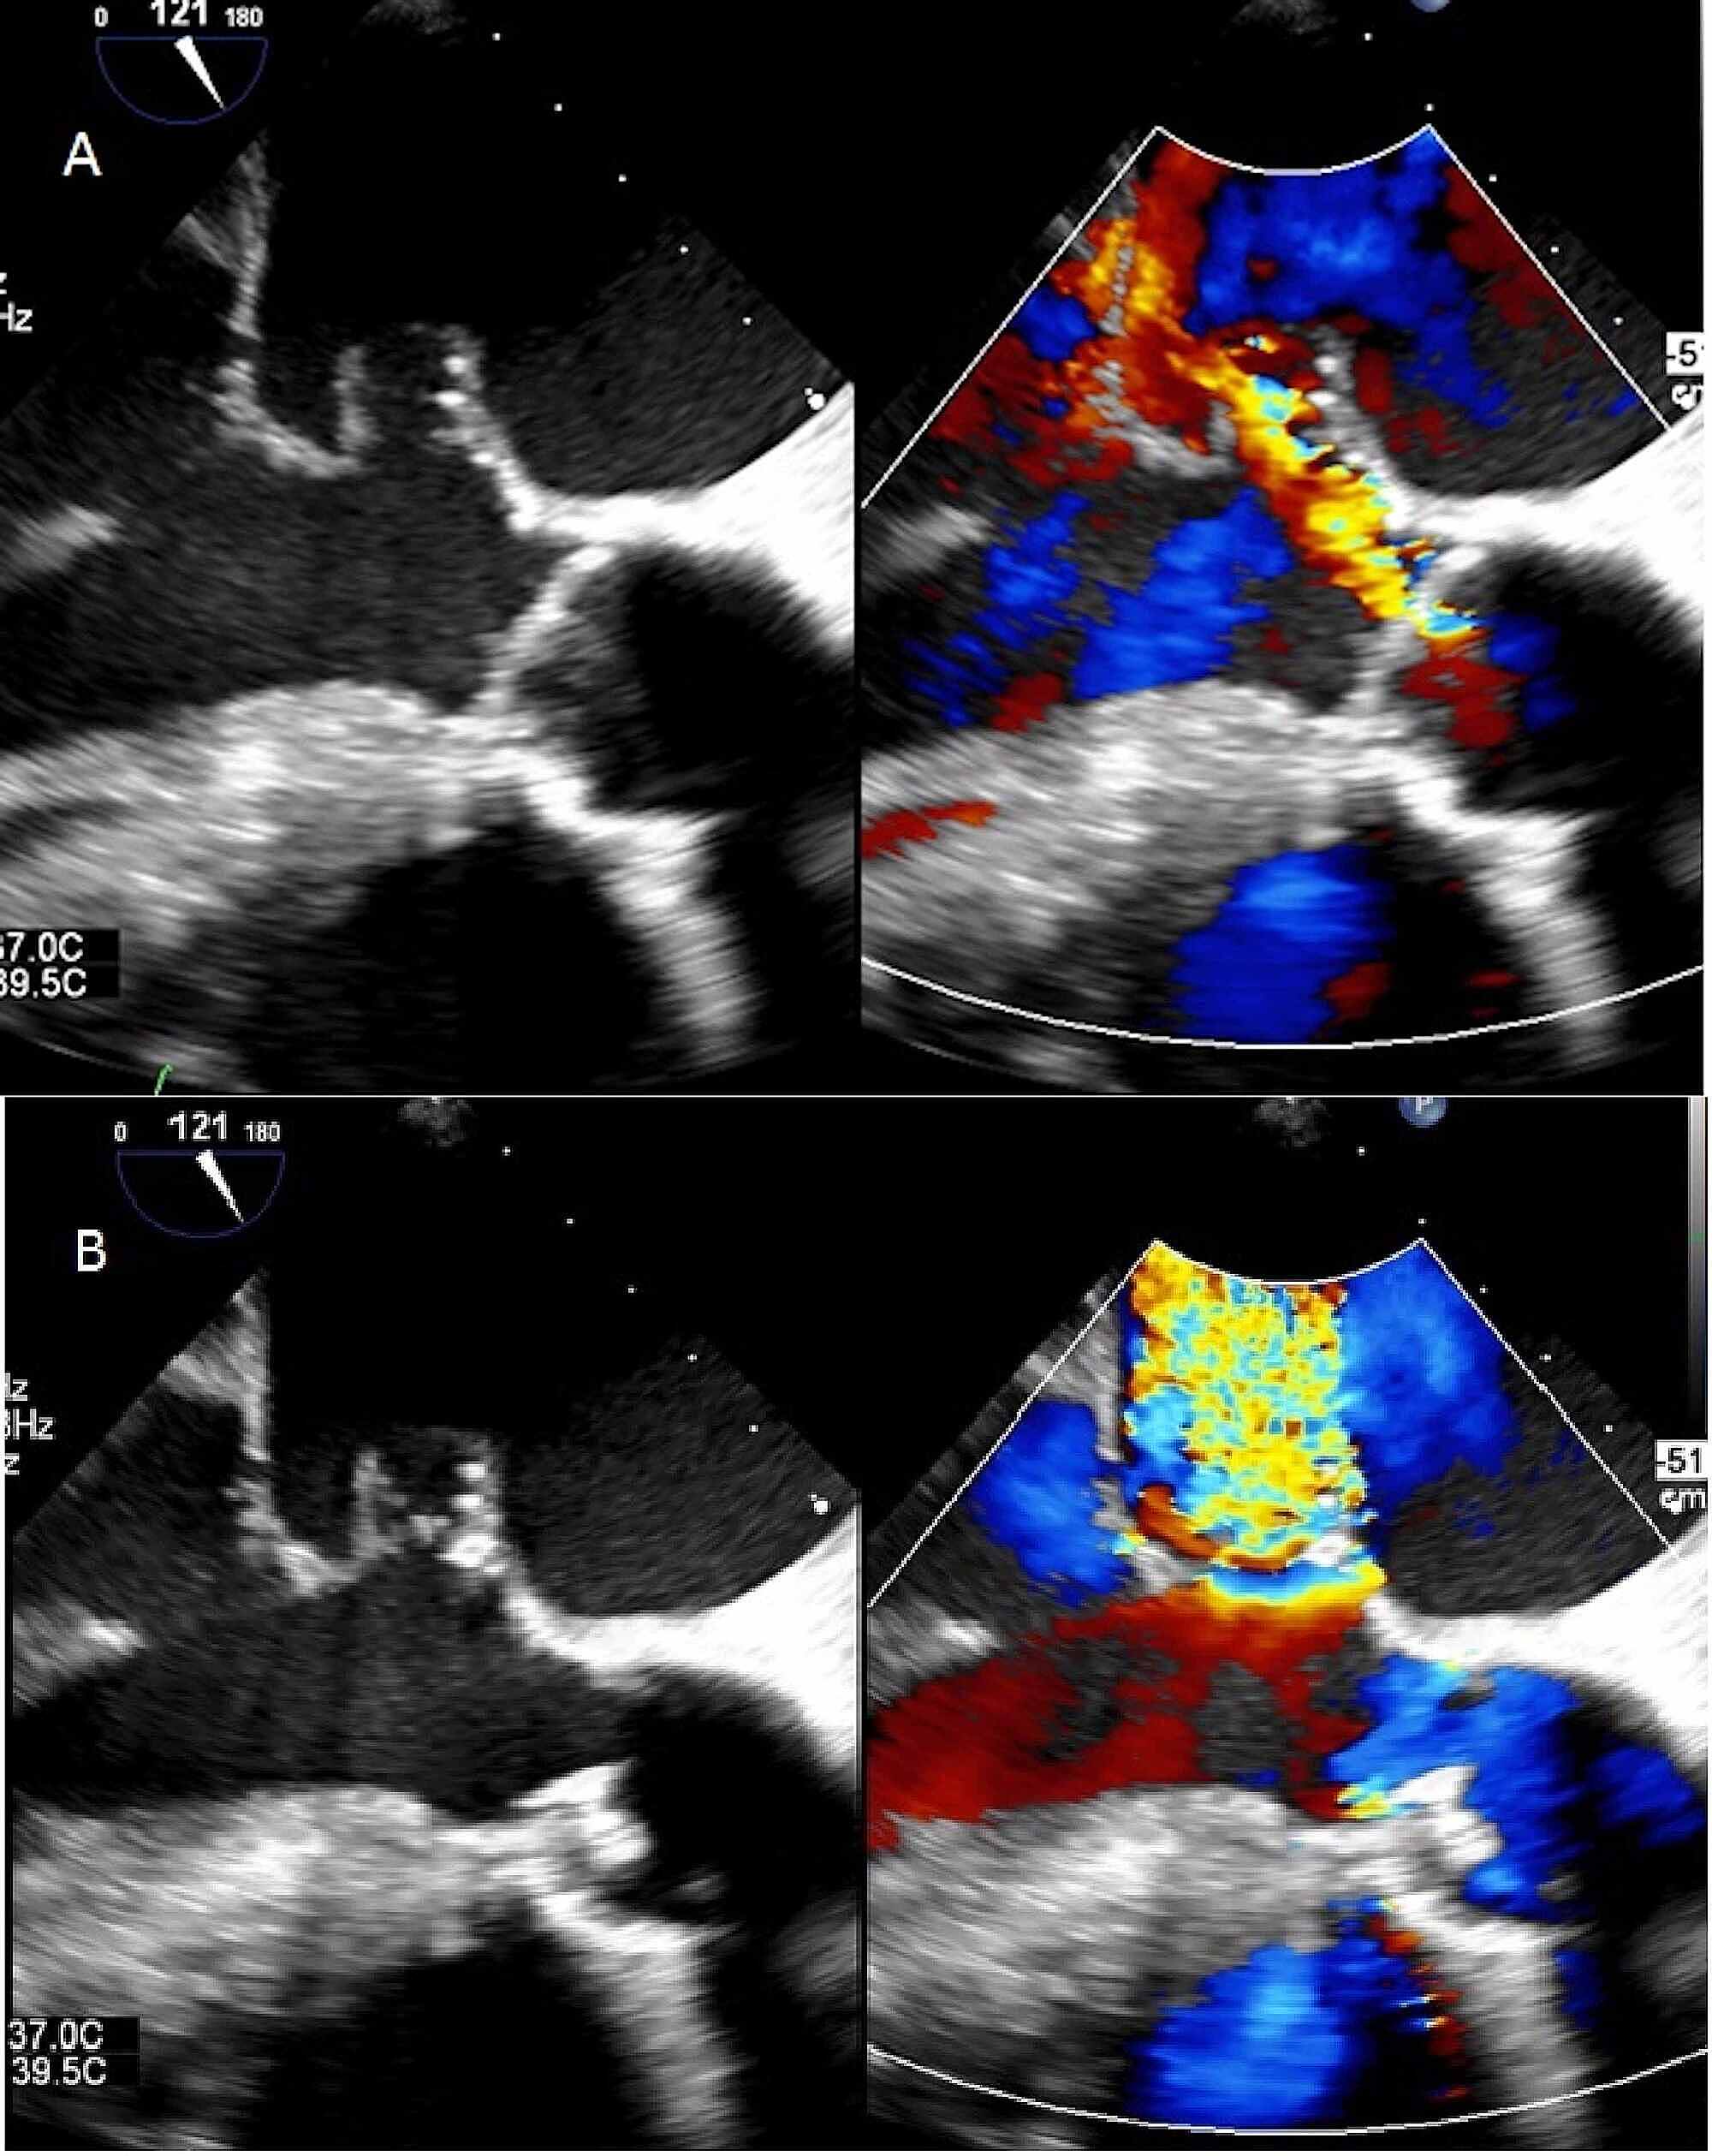

Aortic Valve Prolapse Echo